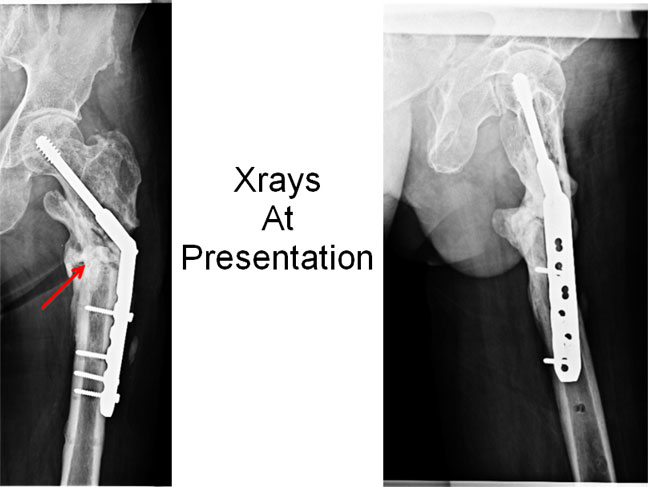

At presentation - 2010

At presentation he still had infection, discharging sinuses with pus draining out (red arrows). Painful limp. Depression. Lack of confidence.

Xrays At Presentation

The x-rays at presentation show loosening of screws, sclerosis at the fracture site, sequestrum (dead necrotic bone) (red arrow).